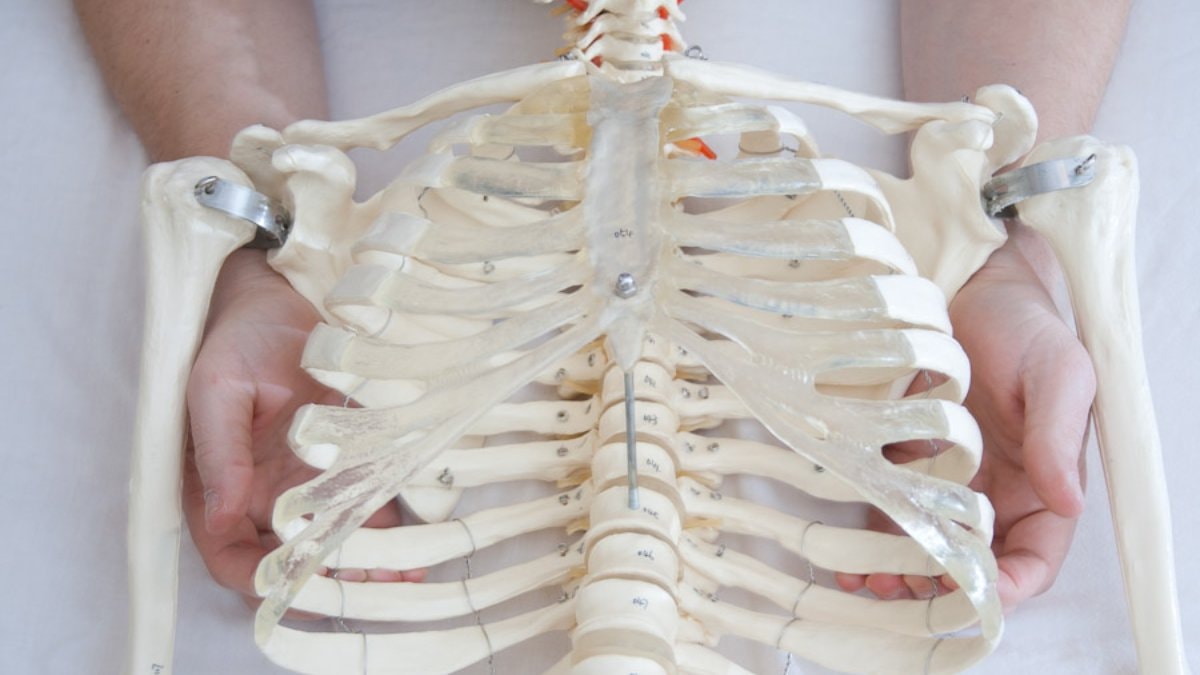

İman tahtası, göğüs kemiği veya iman tahtası kemiği olarak da bilinen sternumun halk arasındaki adıdır.

Sağ ve sol kaburga kemiklerini bir arada tutan göğüs kafesi kemiği, iman tahtasıdır.

Göğüs kafesinin stabilitesini sağlamak: Kaburgaların birleşme noktası olarak, göğüs kafesinin sağlam ve stabil kalmasını sağlar.

Solunum desteği: Kaburgalarla birlikte, solunum sırasında göğüs kafesinin hareket etmesine olanak tanır.